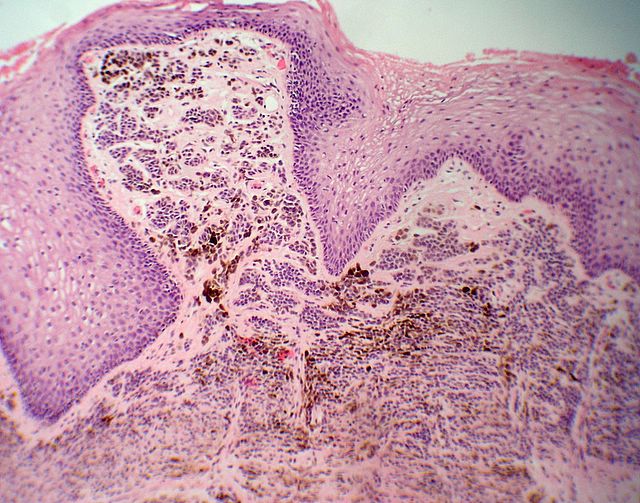

Descripcion histologica

Diagnostico